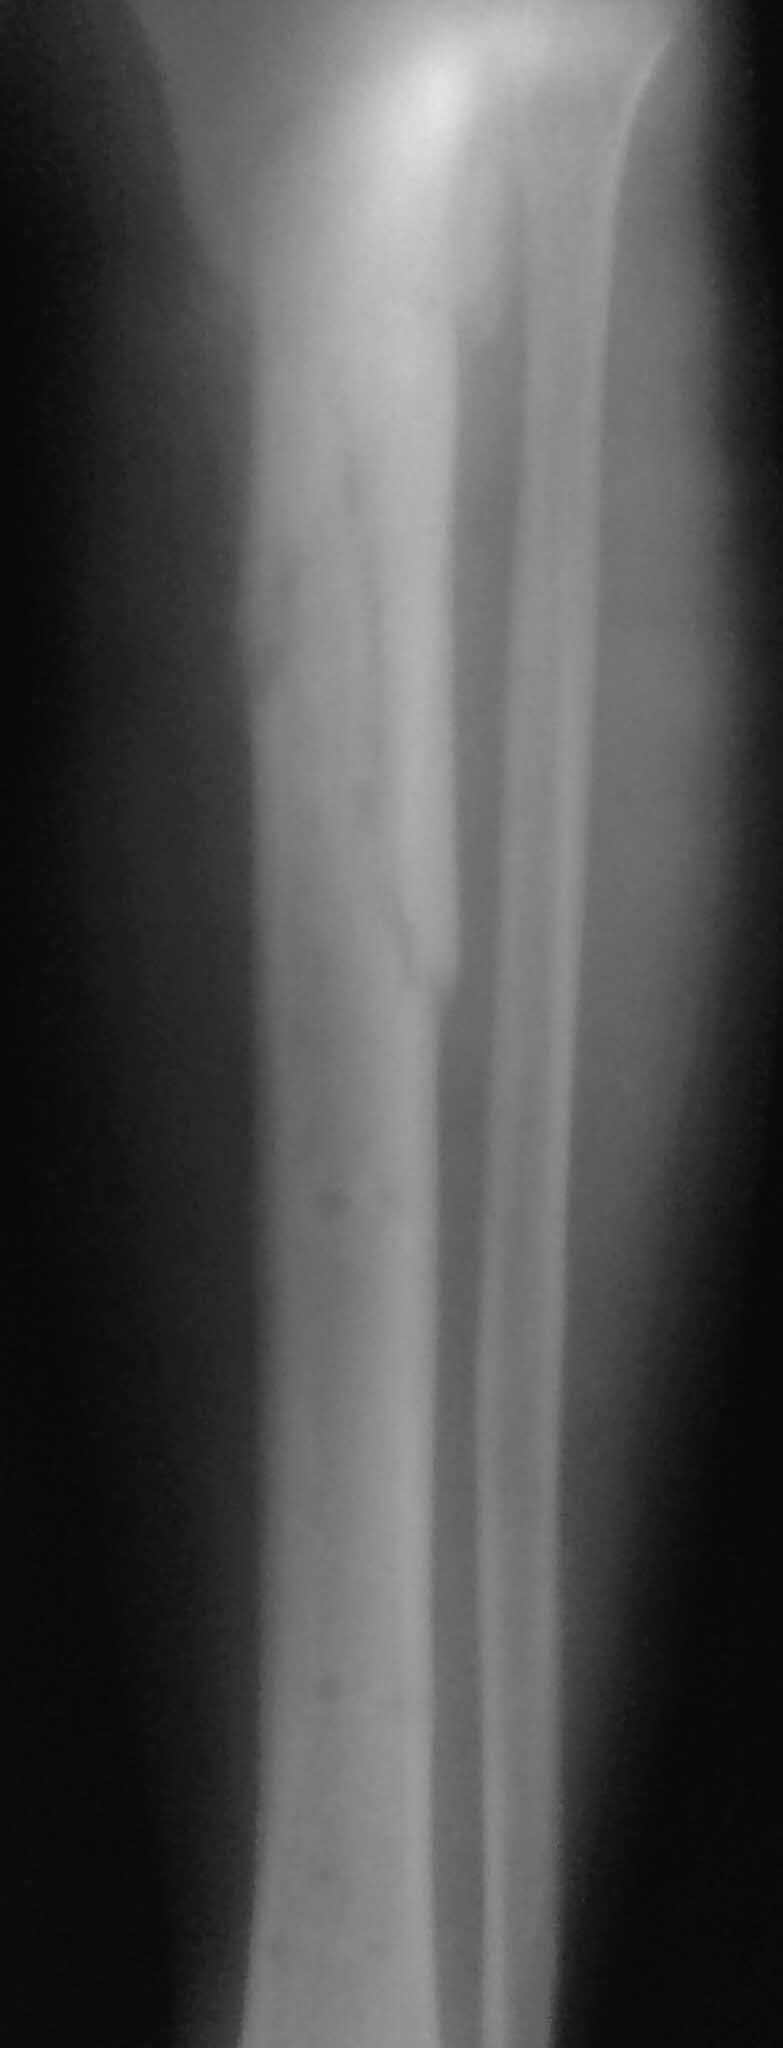

Re: Ложный сустав б/ берцовой с инфицированием

Спасибо за обсуждение.Отправил остальные R, изиняюсь за качество.

3.Перелом на 2 уровнях, есть искривление костно-мозгового канала. Проксимальный отломок короткий.